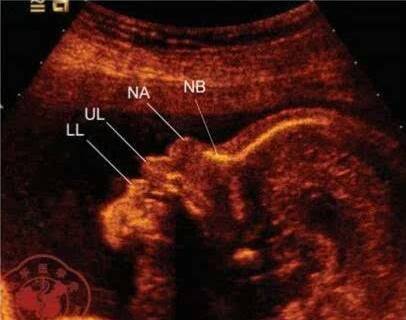

胎儿鼻骨在超声上显示为鼻梁内一条有回声的细线,检测的最佳时间为孕11~13+6周。